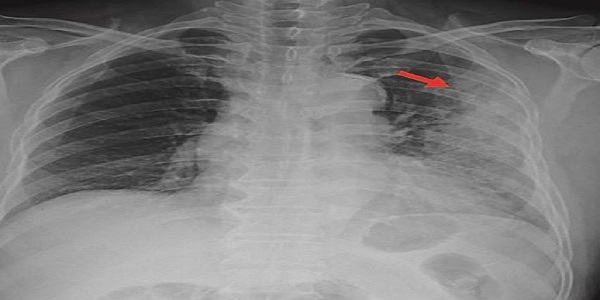

폐렴은 폐 조직에 염증이 생기는 질환으로, 그 원인은 매우 다양합니다. 가장 흔한 원인은 세균 감염이며, 특히 폐렴구균이 가장 흔한 원인균으로 알려져 있습니다. 이 외에도 다양한 세균, 바이러스, 곰팡이, 드물게는 기생충 감염이 폐렴을 유발할 수 있습니다. 바이러스성 폐렴은 인플루엔자 바이러스, 호흡기 세포융합 바이러스(RSV) 등이 대표적이며, 곰팡이 폐렴은 면역력이 저하된 환자에게서 주로 발생합니다. 또한, 화학 물질 흡입이나 음식물, 위산 등이 폐로 잘못 들어가 발생하는 흡인성 폐렴도 있습니다. 폐렴은 발생 양상에 따라 급성 폐렴과 만성 폐렴으로 나눌 수 있으며, 염증의 위치에 따라 대엽성 폐렴, 소엽성 폐렴, 기관지폐렴 등으로 분류하기도 합니다. 폐렴은 누구에게나 발생할 수 있지만, 특히 영유아, 노인, 만성 질환자, 흡연자, 면역력 저하자는 폐렴에 더욱 취약합니다. 폐렴의 원인과 종류에 대한 정확한 이해는 효과적인 치료와 예방을 위해 필수적입니다. 폐렴의 원인을 밝히기 위한 검사로는 객담 검사, 혈액 검사, 흉부 X선 촬영, CT 촬영 등이 있으며, 필요한 경우 기관지 내시경 검사나 폐 조직 검사를 시행하기도 합니다. 폐렴의 종류에 따라 치료 방법이 달라지므로, 정확한 진단과 적절한 치료를 받는 것이 중요합니다.